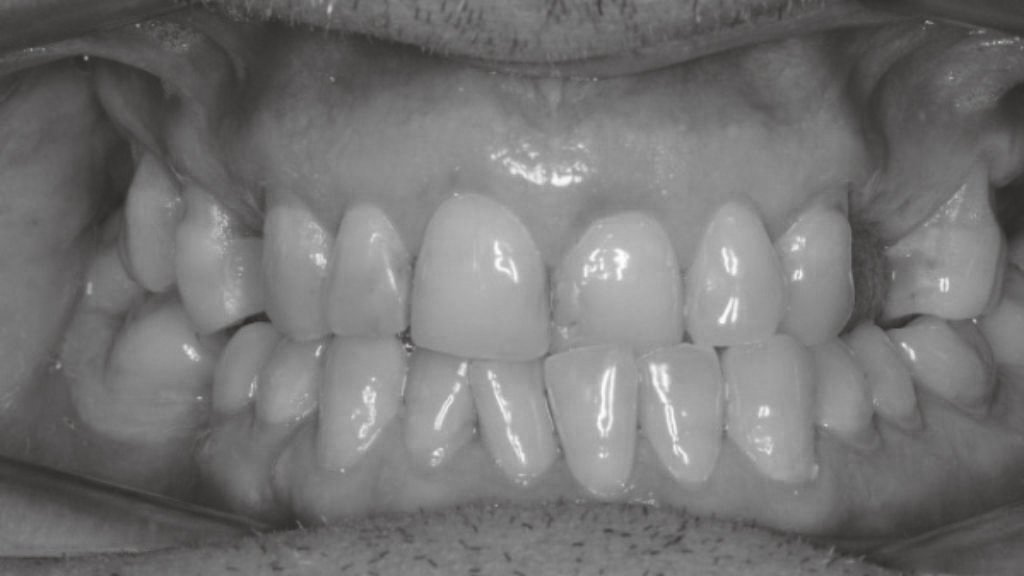

Antes y después en nuestros tratamientos dentales

A continuación te exponemos algunos de nuestros casos de antes y después en implantes dentales, ortodoncia y estética dental.

Antes y después en Blanqueamiento Dental

En un blanqueamiento dental el cambio es sorprendente y la sonrisa se ve rejuvenecida y más atractiva. Gracias a la lámpara Philips ZOOM!, la más avanzada del mercado, el proceso de blanqueamiento es seguro y con resultados duraderos. Se pueden lograr resultados significativamente más eficaces que con los productos de blanqueamiento en el hogar.